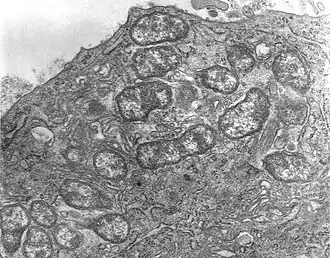

Orientia tsutsugamushi (от яп. ツツガ, tsutsuga — болезнь и ムシ, mushi — насекомое) — вид бактерий из семейства Rickettsiaceae, типовой вид рода ориенций[1] (Orientia)[2]. Возбудитель заболевания, известного как лихорадка цуцугамуши[3]. Является облигатным внутриклеточным паразитом клещей, принадлежащих к семейству Trombiculidae[4][5]. Эндемик так называемого «треугольника цуцугамуши», региона, охватывающего Дальний Восток на севере, Японию на востоке, северную Австралию на юге и Афганистан на западе. Впервые описана Наосуке Хаяси в 1920 году под названием Theileria tsutsugamushi, но в 1995 году переименована в Orientia tsutsugamushi.